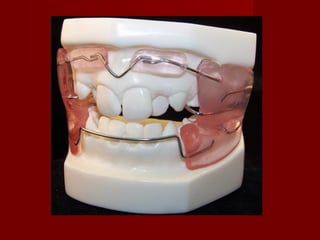

 ( b ) Lower anterior inclined plane( b ) Lower anterior inclined plane

– The bite plane should have sufficient inclination to produce aThe bite plane should have sufficient inclination to produce a

definite forward sliding motion of the maxillary incisor on closure.definite forward sliding motion of the maxillary incisor on closure.

– It may be constructed for a simple tooth on a group of teeth canIt may be constructed for a simple tooth on a group of teeth can

be made of acrylic or cast metal.be made of acrylic or cast metal.

– The appliance is cemented with temporary cement.The appliance is cemented with temporary cement.

– the posterior teeth will be slightly out of the occlusion but thethe posterior teeth will be slightly out of the occlusion but the

discomfort is in the maxillary arch to align the tooth / teeth.discomfort is in the maxillary arch to align the tooth / teeth.

– Pre requisitiesPre requisities

 Enough space in the maxillary arch to align the teeth orEnough space in the maxillary arch to align the teeth or

tooth.tooth.

 the maxillary tooth or teeth to be corrected should bethe maxillary tooth or teeth to be corrected should be

retroclined or eruptin posterior to actual tooth position.retroclined or eruptin posterior to actual tooth position.

 The developmenta status of the mandibular incisors shouldThe developmenta status of the mandibular incisors should

be such that they can tolerate the force generated.be such that they can tolerate the force generated.

 The mandibular incisor should be relatively well aliged toThe mandibular incisor should be relatively well aliged to

allow appliance fabrication.allow appliance fabrication.

 The patient should be cooperative.The patient should be cooperative.